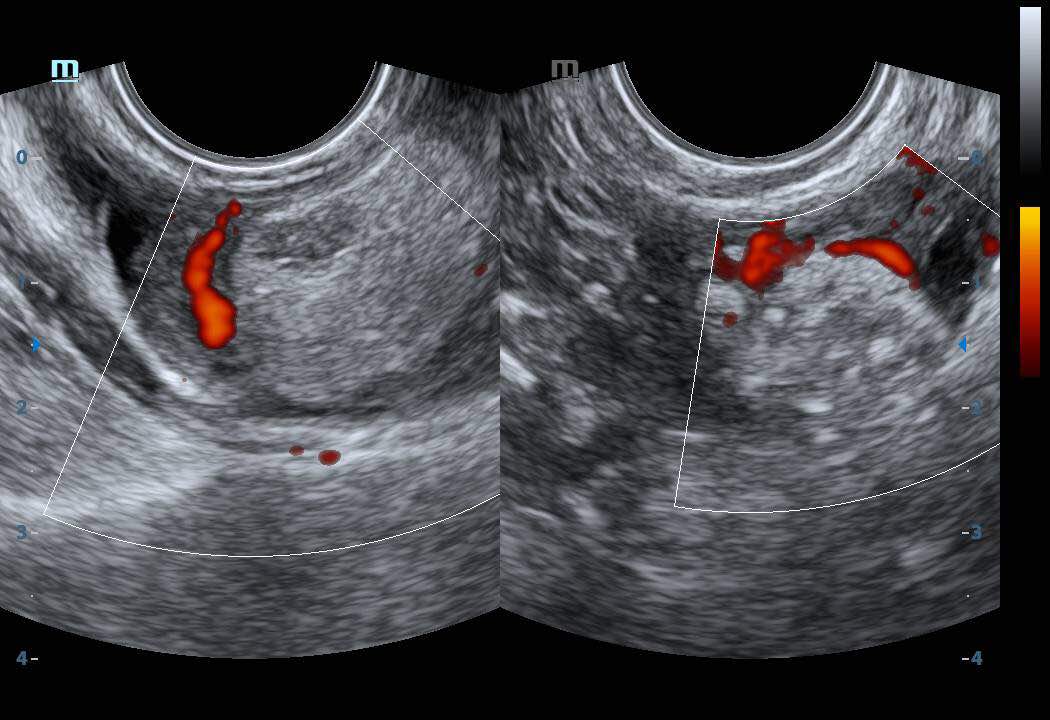

Thickened Endometrium on Transvaginal Ultrasound. Download Scientific Thickened Endometrium Ovaries The appearance, as well as. The normal postmenopausal endometrium should be thin and appear atrophic (see image. In a postmenopausal woman with vaginal bleeding, the risk of cancer is approximately 7.3% if her endometrium is thick (> 5 mm) and < 0.07% if her endometrium is thin (≤ 5 mm). Endometrial hyperplasia thickens your uterine lining, causing heavy or abnormal. Thickened Endometrium Ovaries.